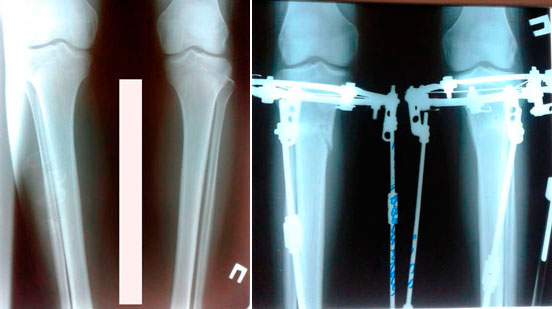

Исходник - 16 лет.

Дата операции - 30.04.2019г.

Дата снятия аппаратов - 23.07.2019г.

Срок сращения - 83 дня.